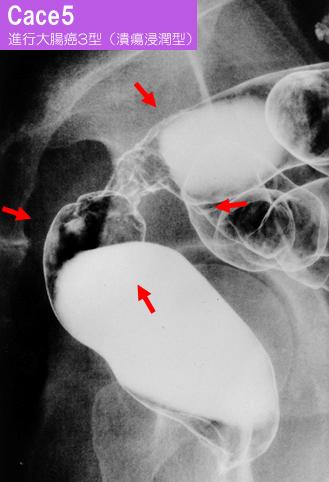

Eight cases of typical advanced colorectal cancer in which each type of radiological images were respectively compared with surgical specimens.

악성 상피성종양/선암

대장/직장

X-P

3형(궤양침윤형)/

40이상

s(a)